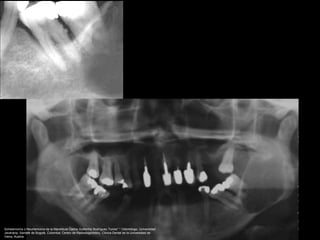

Diagnóstico diferencial

Schwannoma del trigémino, en el cuerpo o en cualquiera de

las ramas.

Schwannoma o Neurilemoma de la Mandíbula Carlos Guillermo Rodríguez Torres* * Odontólogo, Universidad

Javeriana, Santafé de Bogotá, Colombia; Centro de Radiodiagnóstico, Clínica Dental de la Universidad de